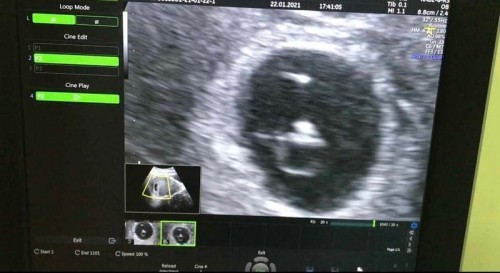

อยากแชร์ไว้เป็นอุทาหรณ์ และเก็บไว้เป็นไดอารี่ เพิ่งตั้งครรภ์ครั้งแรก ตัดสินใจซื้อ urine preg test มาตรวจเอง วันที่ 30/12/2564 ขึ้น เป็นผลบวก (ตั้งครรภ์) จึงมาตรวจครรภ์ที่ รพ.เอกชนชื่อดังประจำจังหวัดแห่งหนึ่ง ถ้านับจากประจำเดือนครั้งสุดท้าย ก็ประมาณ 6 สัปดาห์ และคุณหมอได้ U/S อายุครรภ์ประมาณ 5 สัปดาห์ คุณหมอบอกว่าประจำเดือนเราอาจจะเลื่อน 1 สัปดาห์ จึงนัด U/S อีก 2 สัปดาห์ 2 สัปดาห์ ต่อมา 21/1/2564 มาตรวจ U/S ซ้ำ คุณหมอบอกเห็นเซลล์หลายๆ เซลล์ในถุงตั้งครรภ์ ไม่เห็นหัวใจเด็ก ซึ่งการเห็นเซลล์หลายๆ เซลล์หรือถุงน้ำหลายๆ ในถุงตั้งครรภ์เรา ก็บ่งบอกว่าลูกน้อยในท้องเราผิดปกติ ซึ่งโรคที่คุณหมอนึกถึงคือ Molat pregnancy หรือที่เรียกว่า ตั้งครรภ์ไข่ปลาอุก (คุณพ่อคุณแม่ดูข้อมูลเพิ่มเติมได้ค่ะ https://www.pobpad.com/ครรภ์ไข่ปลาอุก) ซึ่งตัวเราเองพอทราบถึงผลของการตั้งครรภ์นี้ ที่เกิดขึ้นกับลูกซึ่งเด็กไม่สารถเจริญเติบโตได้ และมันมีอันตรายต่อแม่ เสี่ยงเป็นมะเร็งได้ในอนาคต คุณหมอก็ให้ตัดสินใจว่าจะทำอย่างไร 1 รอให้แท้เอง (ซึ่งไม่รู้เมื่อไหร่) 2 ขูดมดลูก/ใช้เครื่องดูด ดูดออก ซึ่งความจริงถ้าตั้งครรภ์ไข่ปลาอุก ต้องทำเลยในขณะที่ตัวอ่อนยังเล็ก เราเห็นแฟนร้องไห้ เครียด เลยขอเลื่อนนัดทำไปก่อน กลับมาที่บ้านเราใช้ droptone ที่ฟังเสียงหัวใจทารก เราเห็น FHS หรืออัตราการเต้นหัวใจทารกแวปๆ ซึ่งเป็นอัตราเต้นปกติ จึงโทรไปปรึกษาเพื่อน เพื่อนแนะนำไป U/S ตรวจซ้ำที่อื่น เราก็ไปตรวจซ้ำ จึงไปตรวจซ้ำที่คลินิกหนึ่ง คุณหมอ U/S ให้ บอกถุงตั้งครรภ์เราปกติ เห็นตัวอ่อนน้อยๆ คุณหมอท่านนี้บอก ไม่ใช่ตั้งครรภ์ไข่ปลาอุกแน่ๆ เราก็สบายใจ และวันนี้ 22/1/2564 ไปตรวจซ้ำที่คลินิกคุณหมออีกท่านหนึ่ง เป็นหมอเฉพาะทาง (Maternal Fetal Medicine (MFM) คือ แพทย์ที่มีความชำนาญเฉพาะทางด้านเวชศาสตร์มารดาและทารกในครรภ์) คุณหมอก็คุยไป ถามประวัติ อาการทั่วไป และหมอก็ U/S ให้ทางหน้าท้อง ก็เห็นถุงตั้งครรภ์ และตัวอ่อนดังรูป เห็นหัวใจเต้นวิบวับ ตามที่คุณหมอบอก 😅 เรารู้สึกดีใจมาก ที่เห็นว่าลูกเราตัวอ่อนกับเจริญเติบโต มีหัวใจเต้นแล้ว 💓 และคุณหมอนัดตรวจครรภ์อีก 4 สัปดาห์เพื่อติดตามเด็กน้อยในท้องเรา 😌😌 **เราเกือบแล้วเกือบตัดสินใจเร็ว เกือบที่จะเอาลูกออก 😣 **อยากแนะนำคุณแม่ หากตรวจครรภ์แล้ว ไม่มั่นใจลองตรวจซ้ำหลายๆ ที่เพื่อคอนเฟิร์ม เรามีสิทธิ์เลือกค่ะ **เราเข้าใจหมออาจวินิจฉัยผิดพลาดได้ แต่มันก็ไม่ควรเกิดขึ้น 😔